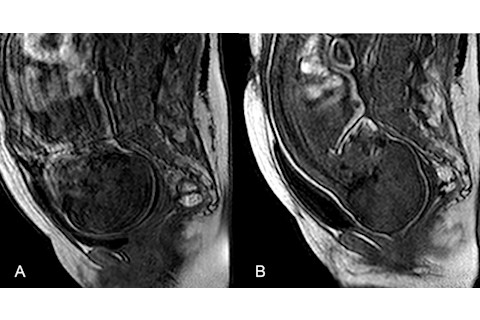

胎儿分娩前(左)和分娩期间(右)的核磁共振图像,显示头骨如何变形。(图片来源:Ami et al./PLOS One)

Ami et al./PLOS One